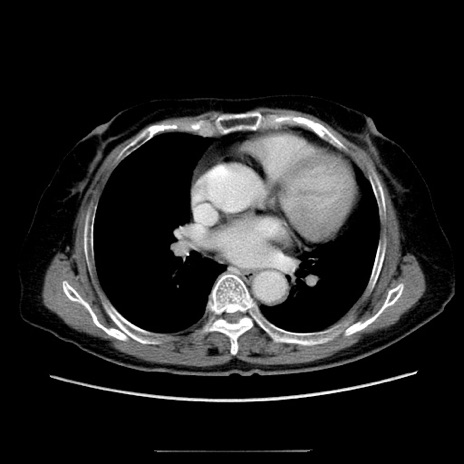

症例5(横断像)

【症例】70歳代女性

【主訴】お腹が張る

【現病歴】1週間くらい前から腹部膨満の自覚あり。昨日夜から増悪したため、本日救急外来受診。

【身体所見】意識清明、BT 36.5℃、BP 165/106mmHg、HR 80bpm、SpO2 98%、腹部:膨満、軟、自発痛・圧痛なし、触診にて不快感あり、腸蠕動音:減弱

【データ】WBC 12600、CRP 1.04